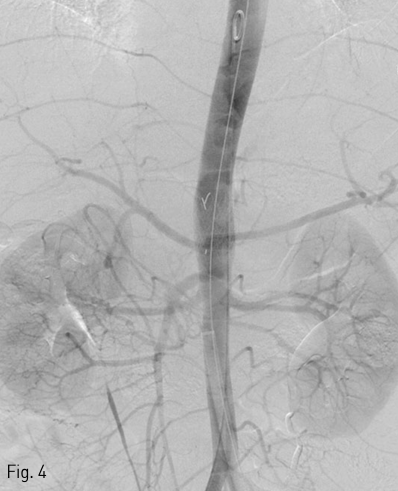

시술 후 거짓동맥류는 소실되었으며, 췌십이지장 연속활(pancreaticoduodenal arcade)를 통한 복강동맥의 가지로의 동맥 혈류는 원활하였음 (Fig. 4).

Fig 4

Completion aortography showed exclusion of previously noted ruptured pseudoaneurysm and patent arterial flow of celiac trunk branches via pancreaticoduodenal arcade.